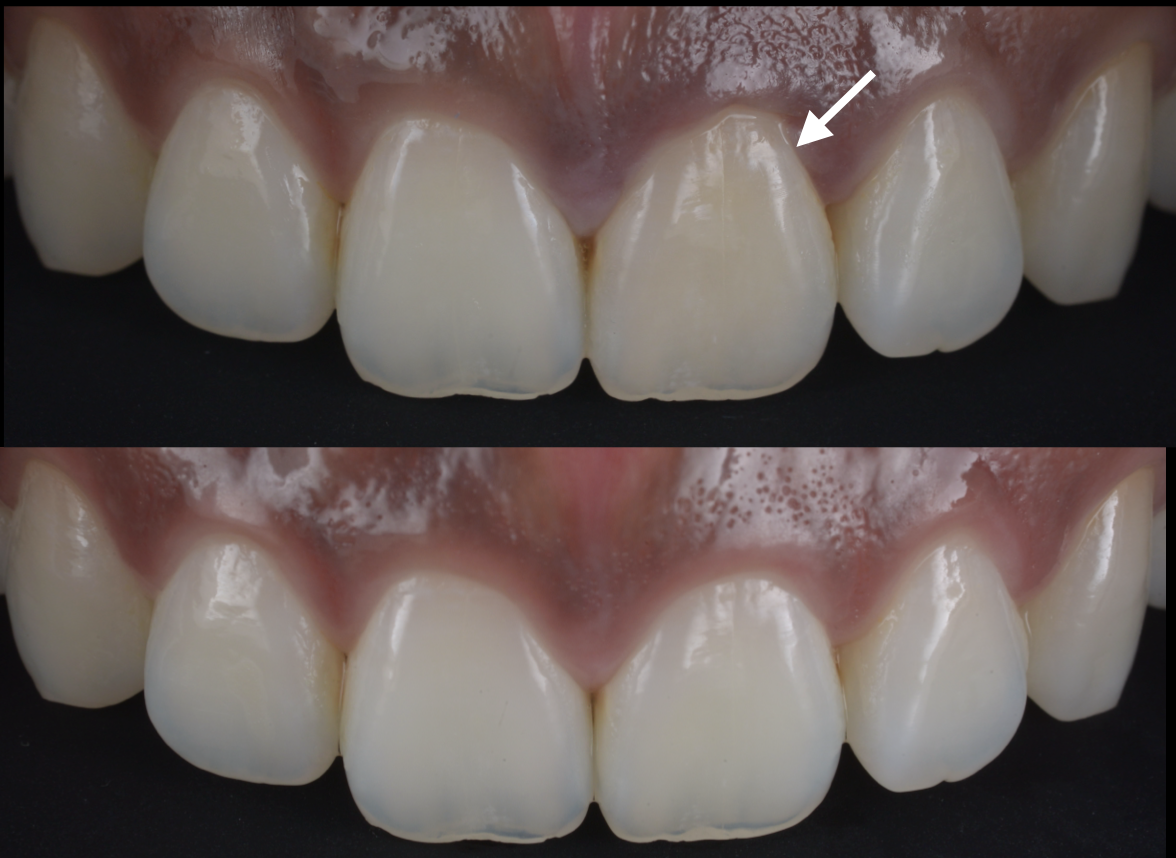

親知らずが腫れて痛いということで当院受診

最小限の侵襲で、粘膜の挫滅や出血が抑えられるように抜歯